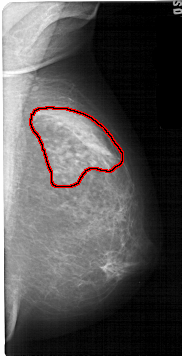

A_1599_1.RIGHT_CC

RIGHT_CC LINES 5416 PIXELS_PER_LINE 2956 BITS_PER_PIXEL 12 RESOLUTION 43.5 OVERLAY

FILE: A_1599_1.RIGHT_CC.OVERLAY

TOTAL_ABNORMALITIES 1

ABNORMALITY 1

LESION_TYPE MASS SHAPE ASYMMETRIC_BREAST_TISSUE MARGINS OBSCURED

ASSESSMENT 2

SUBTLETY 5

PATHOLOGY BENIGN_WITHOUT_CALLBACK

TOTAL_OUTLINES 1

BOUNDARY